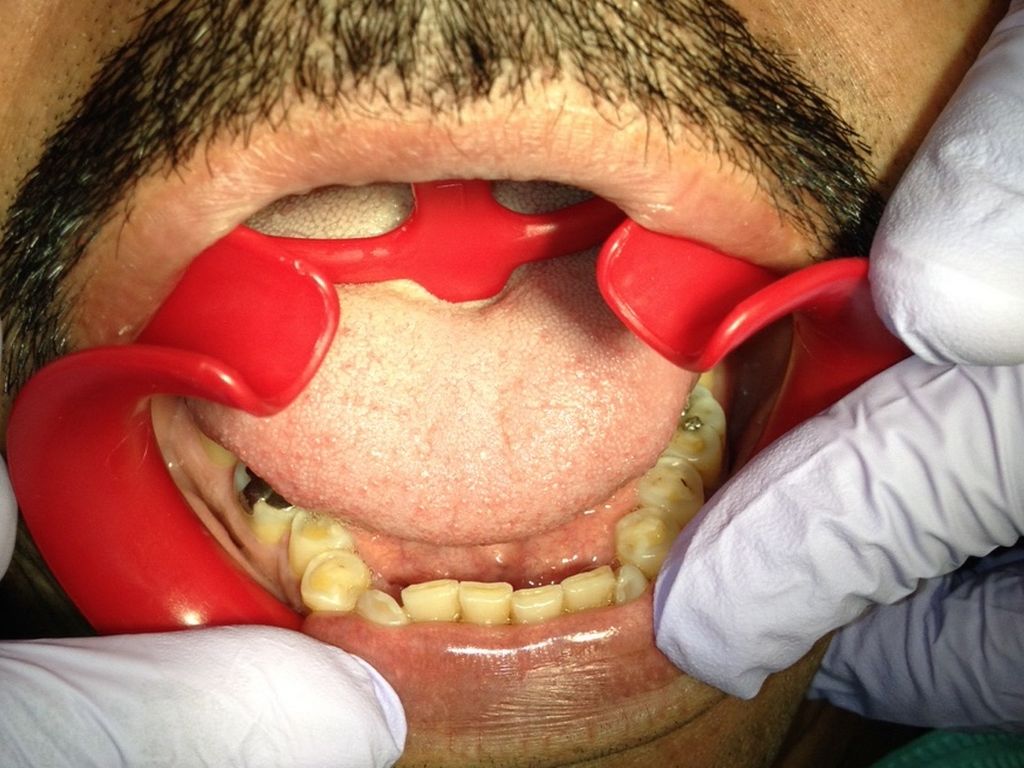

SAY AAAAHHH

41 year old male.

No known drug allergies or medications.

Chief Complaint: "I have fake teeth in front but I want them glued back."